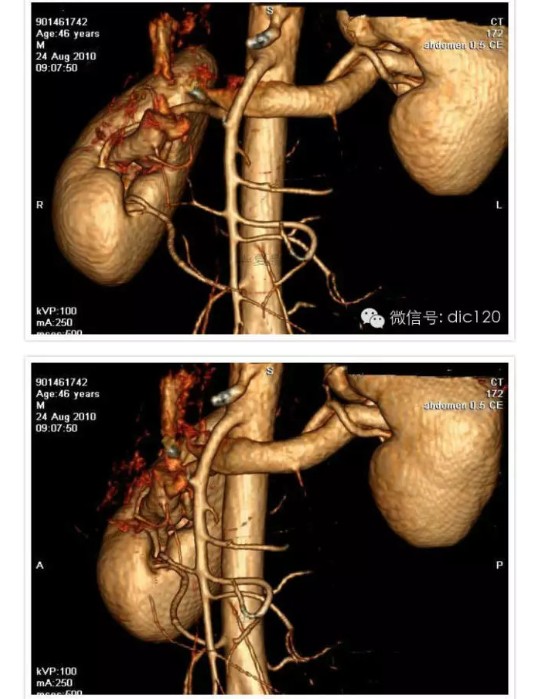

胡桃夹综合征(nutcracker phenomenon)即左肾静脉压迫综合征,又称胡桃夹现象,好发于青春期至40岁左右的男性,儿童发病分布在4~7岁,多发年龄见于13~16岁。 左肾静脉行走在腹主动脉和肠系膜上动脉之间,这两条动脉构成40~60度的夹角,左肾静脉刚好通过此夹角。从解剖上看,右肾静脉径直注入下腔静脉,行程短而直,而左肾静脉需穿过腹主动脉和肠系膜上动脉之间的夹角,跨越腹主动脉前方始能注入下腔静脉,因此左肾静脉远较右肾静脉长。正常时,肠系膜上动脉与腹主动脉之间的夹角被肠系膜、脂肪、淋巴结和腹膜等所充塞,使左肾静脉不致受到压挤。当青春期发育较快、身高迅速增长、脊柱过度伸展、体形急剧变化或肾下垂等情况下,左肾静脉在这个夹角中受到挤压,引起血流变化和相应的临床症状。 胡桃夹现象的主要症状是血尿和蛋白尿,其中无症状肉眼血尿更易发现。血尿的原因是左肾静脉受压致肾静脉高压,左肾静脉扩张所引流的输尿管周围静脉与生殖静脉淤血、与肾集合系统发生异常交通,或部分静脉壁变薄破裂,引起非肾小球性血尿,还会发生睾丸静脉和卵巢静脉淤血而出现肋腹痛,并于立位或行走时加重。另外男性还能发生精索静脉曲张。此外有蛋白尿,不规则月经出血,高血压等。此病的诊断标准为:一侧肾出血;尿红细胞形态为非肾小球性;尿中钙排泄量正常;膀胱镜检查为左侧输尿管口喷血或血性尿;腹部彩超或CT检查可见左肾静脉扩张等。